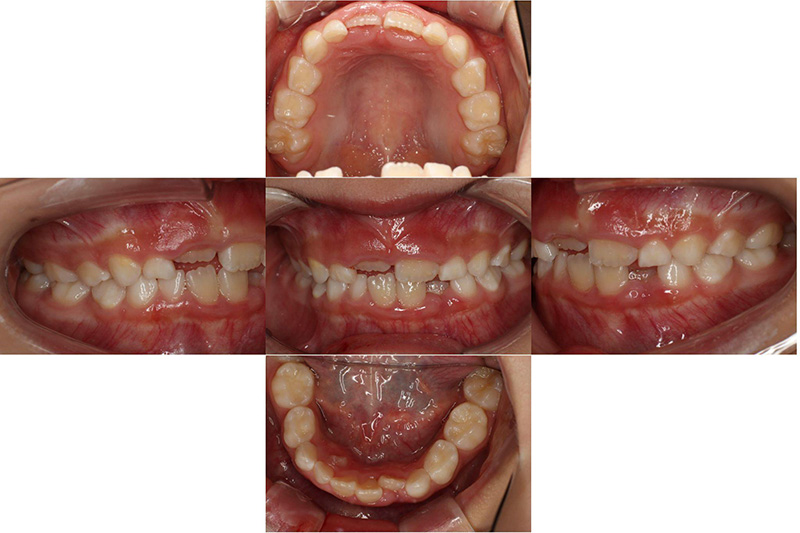

治療前

治療後

| 治療内容 | プレオルソタイプ3を日中1時間と夜間就寝時装着それに加え口腔周囲筋のトレーニング |

|---|---|

| 治療期間・回数 | 約12ヶ月、10回 |

| 費用 | 約11万円 検査費用含む |

| 副作用リスク | 後戻り 歯の痛み 歯の動揺 咬合違和感 |